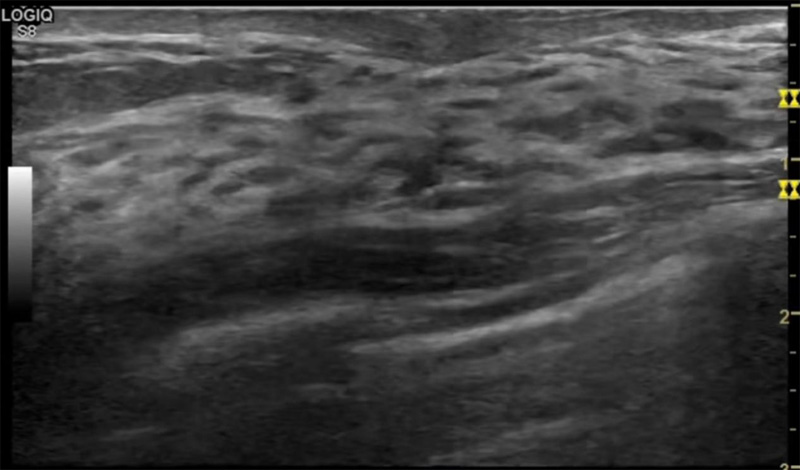

乳房脹痛,觸摸疼痛,手摸起來感覺有腫塊。這個是什么問題呢?醫生診斷一般是乳腺增生。那么在乳腺超聲設備檢查后,報告單卻顯示雙乳未見明顯占位性病變。乳腺增生是很多女性,特別是育齡期女性都有的經歷、到底乳腺增生癥狀有哪些?會給我們帶來怎樣的影響呢?乳腺增生不是腫瘤跟炎癥。乳腺組織增生及退行性變跟內分泌功能紊亂有關系。正常的生理改變。還有乳腺病,良性乳腺結構不良等名稱。

乳腺增生有什么癥狀,病因?比較典型的就是乳房疼痛,特別是經前癥狀比較重,經后就有所緩解。有時候還能碰到乳房硬塊。根據經期的變化而變化硬度大小都有變。乳腺在內分泌激素,伴隨月經周期有增生問題。內分泌激素代謝失衡,雌激素水平增高,出現乳腺組織增生過度,增生組織不退的情況下,就會有乳腺增生癥狀。這個不會增加乳腺癌的風險。所以不用緊張的。不過乳腺癌的病人都會有乳腺增生。所以乳腺增長有沒癥狀,都需要進行常規的體檢。

乳腺超聲設備便捷安全的檢查方法,國際上有乳腺檢查超聲的指南。可以針對乳腺疾病做出系統的分類。《乳腺超聲若干臨床常見問題專家共識(2018版)》說明不建議提示乳腺增生癥。單純的囊腫,乳腺改變等。在BI-RADS分類中已經納入不同類別。針對未發現占位的乳腺,雙乳未見占位性病變(BI-RADS 1類)。因此看到這樣的檢查報告時候,不用緊張擔心,占位性結節沒有形成。